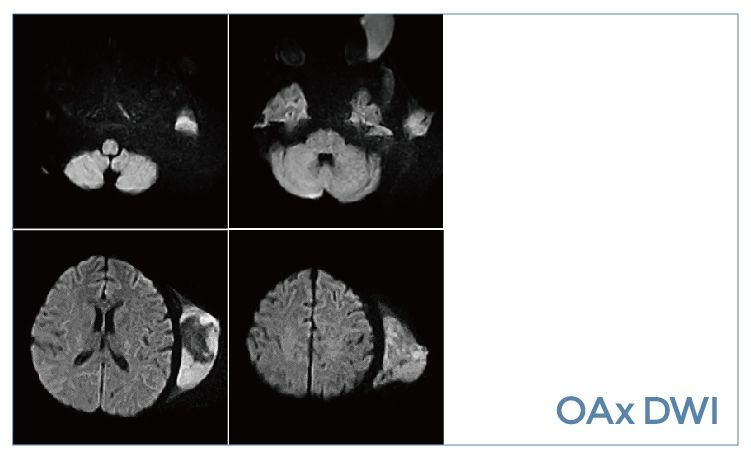

【朗润影像档案】20190920磁共振影像病例结果讨论